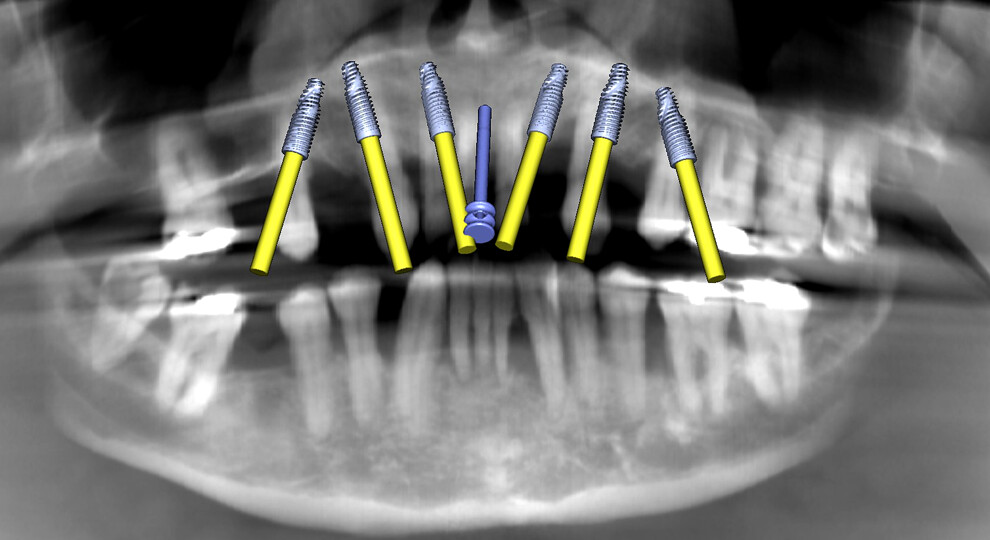

Fig. 2b: Maxillary implant simulation on the panoramic radiograph showing six implants and a nasopalatine canal pin.

The initial plan for the maxillary arch was to remove all the remaining natural teeth, place six implants and employ bone grafting material where necessary to fill the sockets and other concavities or fenestrations. The simulated implants were visualised on the panoramic reconstruction, including an anchor pin located at the midline engaging the nasopalatine canal (Fig. 2b). Using advanced features to distinguish between objects based on their radiodensity, interactive treatment planning software (Blue Sky Plan) and user-defined selective transparency, the simulated implants could be fully appreciated within a 3D rendering of the maxillary bone (Figs. 3a–c).